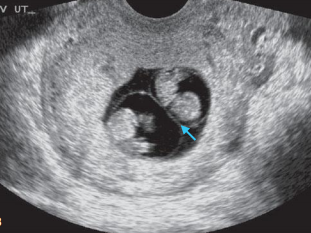

多年来,贵州航天医院各科室紧跟医学前沿,不断强技术、补短板,大力开展新技术、新项目,完成了许多高精尖、高难度、本地区“首例”的技术,填补了医院医疗技术空白,满足了群众日益增长的医疗需求。 复杂性双胎超声监护耗时耗力,技术难度大,风险高,为填补本地区复杂性双胎的超声监护技术空白,我院超声科在遵义市率先开展了此项技术,有效满足了双胎孕妇产检需求,保障了双胎新生儿的平安健康。 本期,我们将为大家带来超声科特色技术——复杂性双胎的超声监护。 案例分享 案例一 28岁的孕妇,自然受孕,怀有单绒毛膜双羊膜囊双胎(MCDA),在我院定期产检的过程中,孕32周超声检查发现两个胎儿的大脑中动脉血流流速(MCA-PSV)相差>0.7倍数的正常值(MoM),高度怀疑发生了双胎贫血红细胞增多序列征(TAPS)。为进一步明确诊断,产科立即组织超声科、手术室、新生儿科等科室进行多学科会诊(MDT),诊断为:双胎贫血红细胞增多序列征(TAPS),在征得孕妇及其家属的同意后,决定提前分娩,及时保障了两名胎儿的生命和健康。 双胎大脑中动脉血流 双胎贫血红细胞增多序列征(TAPS) 案例二 一名26岁的孕妇,是完全双角子宫,且为左侧子宫妊娠,怀有单绒毛膜双羊膜囊双胎(MCDA),一直在我院规律产检,孕16周时,超声检查发现双胎生长不一致,体重相差超过25%,考虑子宫畸形合并早发选择性胎儿宫内生长受限。孕妇在咨询相关上级医院专家后,得到减胎的建议,又前来我院咨询,在我院超声科和产科的合作下,查阅了大量文献、认真评估检查报告后,建议孕妇继续双胎妊娠。在规律、严密的超声监护下,双胎除体重差异外未出现严重胎儿并发症,在34周进行了分娩,截至目前,新生儿生长发育均正常。 胎儿生长曲线及子宫畸形三维重建 出生时体重差异 十月龄时 案例三 一名30岁的孕妇,自然受孕,怀有单绒毛膜双羊膜囊双胎(MCDA),在孕22周时超声检查发现双胎发生了选择性胎儿宫内生长受限,遂转诊到上级医院拟行胎儿镜治疗,但在行治疗的前一天,较小的胎儿在宫内发生死亡,在充分与孕妇及家属沟通后,要求继续妊娠,在定期规范的产检下,严密监测胎儿生长发育及胎儿颅脑MRI影像,最终在孕37周时通过剖宫产分娩,目前新生儿生长发育情况良好。 双胎之一胎死宫内(右图) 贵州航天医院自2021年开展复杂性双胎的超声监护以来,已服务大量双胎孕妇,集齐了所有单绒毛膜双羊膜囊双胎(MCDA)并发症病例,由经验丰富的超声医师进行此项检查,产科专业团队进行双胎的规范化监护和分娩,并与重庆医科大学附属第一医院建立了转诊通道,能够及时获得该院专家的指导和支持,为广大孕产妇提供优质、全面的医疗保障。 点击跳转贵州航天医院便民服务电话 什么是复杂性双胎的超声监护 “双胎”被称为产科之王,单绒毛膜双胎则为王中王,主要是因为单绒毛膜双羊膜囊双胎(MCDA)两胎儿共用一个胎盘,胎盘中存在血管吻合。 双胎妊娠的产前筛查及诊断主要依靠超声,相对于单胎妊娠,双胎妊娠并不是单胎检查的重复,双胎妊娠尤其是复杂性双胎的超声诊断更为重要的是关注双胎间循环的关联,双胎间生理及病理改变的相互影响,双胎间血流动力学监测及双胎间差异比较。 超声如何诊断 复杂性双胎并发症 在孕14周以前,超声要明确双胎的绒毛膜性:是单绒毛膜(MC)还是双绒毛膜(DC);孕10周前,可以通过孕囊的个数确定绒毛膜性;孕11周—14周,可以通过胎儿的性别、双胎之间隔膜的厚度、双胎儿分隔膜处胎盘的形态等来区分绒毛膜性。 双绒毛膜双胎的管理和单胎差不多,基本不需要增加超声检查的频次。单绒毛膜的管理相对谨慎,按照国际国内指南规范,单绒毛膜双胎自第16周起,每两周对双胎儿进行生长发育评估及血流检查。 复杂性双胎的超声监护,对超声医生技术要求较高,孕早期需对双胎的绒毛膜性进行精确判断;产科医生根据绒毛膜性制定孕期的产检计划;超声医生掌握胎儿宫内情况,及时与产科医生沟通,精确了解胎儿宫内安危后制定合适的治疗方案,给出适当的终止妊娠时机;复杂性双胎一般都面临早产的风险,所以新生儿团队的专业保障不可或缺,降低新生儿出生后的并发症及提高新生儿生活质量。复杂性双胎的较好妊娠结局,是通过孕期超声科、产科紧密合作,及新生儿出生后新生儿科管理多学科团队合作所获得的。 贵州航天医院超声科专家团队 吴艳辉 超声科 学科带头人 主任医师 专业擅长:从事超声诊断工作约30年,对心血管、小器官超声、超声引导下介入等具有丰富的临床经验。 骆科美 超声科 副主任医师 专业擅长:从事超声诊断工作33年,对胎儿心脏及颅脑、妇产超声诊断、盆底超声等诊断具有丰富的临床经验。 胡大海 超声科 副主任医师 专业擅长:从事超声工作17年,对心血管、外周血管、浅表器官超声诊断等具有丰富的临床经验。 刘 敏 超声科 副主任医师 专业擅长:从事超声诊断工作20余年,对妇产科超声、心脏血管超声诊断具有丰富的临床经验。 贵州航天医院超声科简介 贵州航天医院超声科配备多种超声检查设备(飞利浦彩超(IU-22、IU-Elite、HD11、Q5、Q7),迈瑞超声I9、DC-6、DC-8、GE-E8及床旁机,彩色超声诊断仪等),设有心血管诊室、妇产科诊室、腹部诊室、绿色通道、浅表小器官等检查室。 • ✦ 专科特色 ✦ • 四肢血管超声检查、双胎产前筛查及超声监护、超声造影检查技术、介入超声临床应用、经颅脑实质超声辅助筛查诊断帕金森病、女性性早熟超声诊断、盆底超声检查等。 NT超声检查 超声介入引导 肝脏超声造影 甲状腺造影 颅脑超声帕金森辅助检查 乳腺超声造影 上肢动静脉造瘘超声检查 双胎超声筛查 下肢血管超声检查 右心造影 • ✦ 诊疗范围 ✦ • 科室业务覆盖腹部、泌尿、妇科、产科(常规、NT筛查、III级筛查超声检查及高危妊娠监护)、成人心脏、外周血管、浅表器官(包含甲状腺、乳腺、阴囊、眼睛等)、颅脑(小儿颅脑、成人颅脑)、小儿肺超、造影、盆底、腹直肌、肌骨神经等检查及各种介入引导。